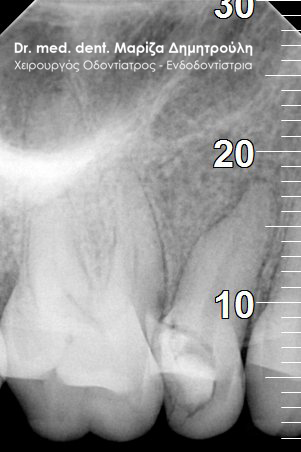

Περιστατικά – Απονεύρωση δοντιού

Παρακάτω παρατίθονται μερικά περιστατικά μετά την ολοκλήρωση της απονεύρωσης δοντιού.

Κάτω γομφίος με κεκαμμένες ρίζες

Άνω γομφίος με έντονα κεκαμμένες ρίζες

Μονόριζο δόντι με 3 ριζικούς σωλήνες

Κάτω γομφίος